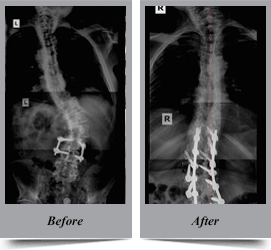

Congenital Scoliosis

Congenital scoliosis is the lateral curvature of spine that occurs in children